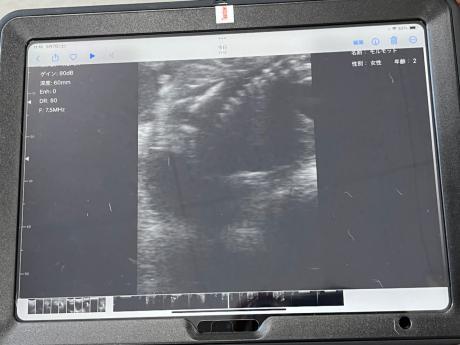

9月7日にエコー検査で胎児の確認を行いました。

お腹に当てているのがエコーの機械で、奥のタブレットに映像が映ります。

エコー画像がこちらです。

少し分かりずらいかもしれませんが、

右上に写っている点線のようなものが胎児の背骨です。

これがエコー検査で3つ確認できたので、お腹の中に胎児が3頭いることが分かりました!